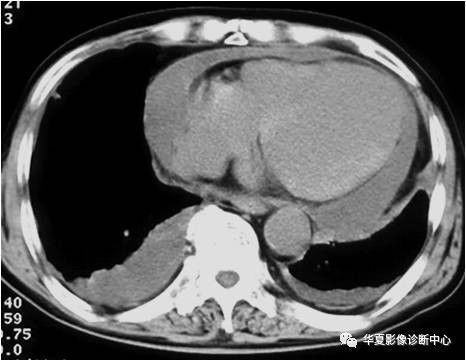

【影像基础】CT也可大致定量心包积液

466x361 - 25KB - JPEG